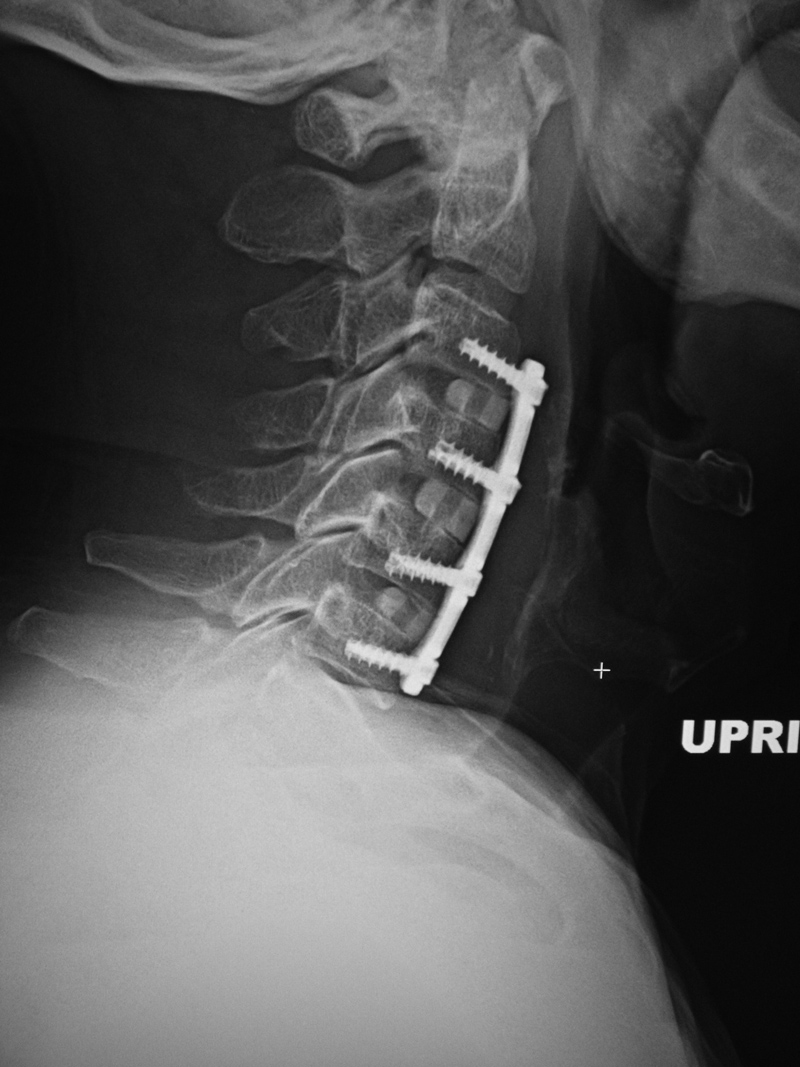

Young woman with traumatic locked facets at C6-7 and C7 body fracture. A posterior cervical fusion with lateral mass screws (cervical spine) and pedicle screws (thoracic spine) and rods extends from C4 to T2. There is an anterior cervical fusion plate and screws at C6-7 with a intervertebral disk cage at C6-7 and a crosslink at C6. There is an anterior cervical fusion plate that extends from C3 to C7 and posterior lateral mass screws and rods on each side from C3 to C7. Intervertebral bone struts (plugs) are present at the disk spaces from C3 to C6.

Anterior and posterior cervical spine fusion AP view Anterior and posterior cervical spine fusion lateral view Anterior and cervical spine fusion with intervertebral bone struts Anterior and cervical spine fusion with intervertebral bone struts

Cervical spine anterior and posterior fusion Cervical spine anterior and posterior fusion with intervertebral bone struts (plugs)